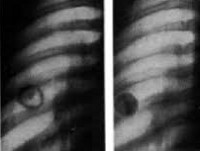

Основой для верификации диагноза остается рентгенография легких. Характерный рентгенологический признак - наличие ограниченного затемнения правильной округлой формы, с четкими контурами и преимущественно однородной структурой. В стадии обострения контуры туберкуломы легкого становятся размытыми за счет появления перифокальной инфильтрации.